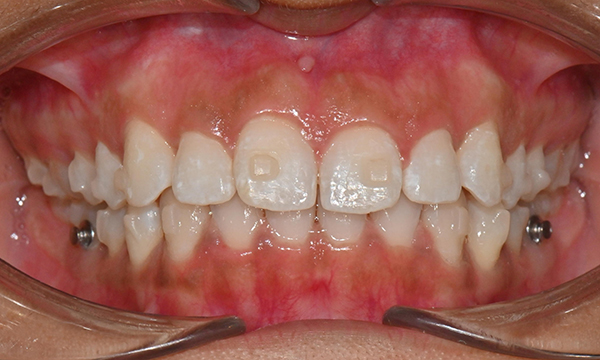

위아래 앞니 사이가 벌어져서 공간이 있었고, 앞니에 약간씩 배열이 틀어진 덧니가 있었습니다. 정면에서 보았을 때 윗니와 아래 앞니가 깊게 물려서 아래 앞니가 잘 보이지 않는 과개교합 양상을 보이고 있었습니다. 또한 왼쪽 아래 작은 어금니가 90도 앞으로 돌아가서 좌측 치아 배열 및 교합이 좋지 않은 상태였습니다.

초진시 구내사진 (2025. 3.31)